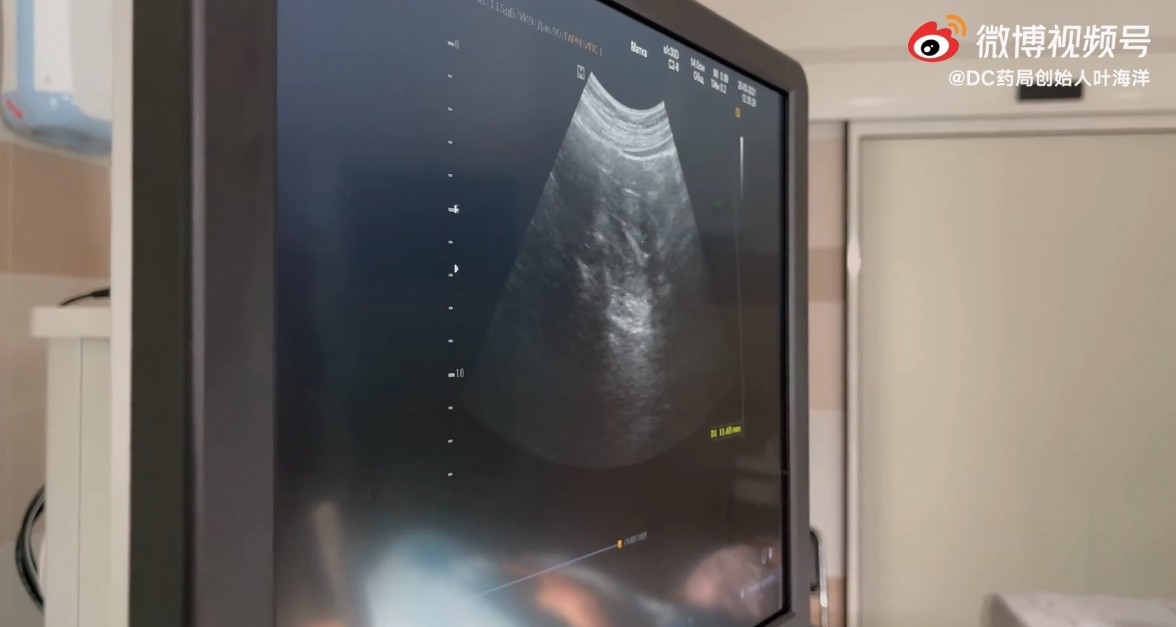

現年33歲、作為家中獨生女的葉海洋,因為「怕孩子未來覺得孤單」,最近就拍片紀錄自己飛往俄羅斯做「第二胎」試管嬰兒手術的心路歷程。葉海洋更指,自己心中早已有想為 Doris 添上弟弟妹妹的計劃,不過受到疫情的影響,才將計劃一推再推,最後更決定改到較安全的俄羅斯進行手術。